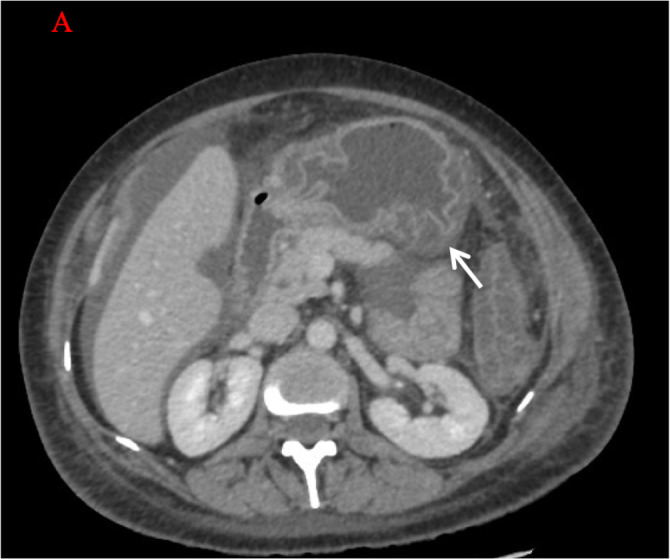

Lupus enteritis is a rare gastrointestinal complication of systemic lupus erythematosus (SLE) associated with significant morbidity and mortality. Rituximab, a monoclonal antibody targeting CD20-positive B cells, has shown promise in refractory SLE cases. We present a case of a 45-year-old female with SLE who developed lupus enteritis and experienced an unusually rapid and remarkable response to Rituximab. The patient presented with severe abdominal pain and distension. Within two days of Rituximab treatment, the patient's abdominal pain, distension, and associated complications resolved completely. This exceptional response challenges the typical timeline of Rituximab efficacy in SLE and highlights the need for further investigation into the factors influencing treatment response. Understanding the mechanisms underlying such rapid improvement may provide insights into SLE pathogenesis and guide therapeutic strategies for optimal outcomes.

Abstract Image